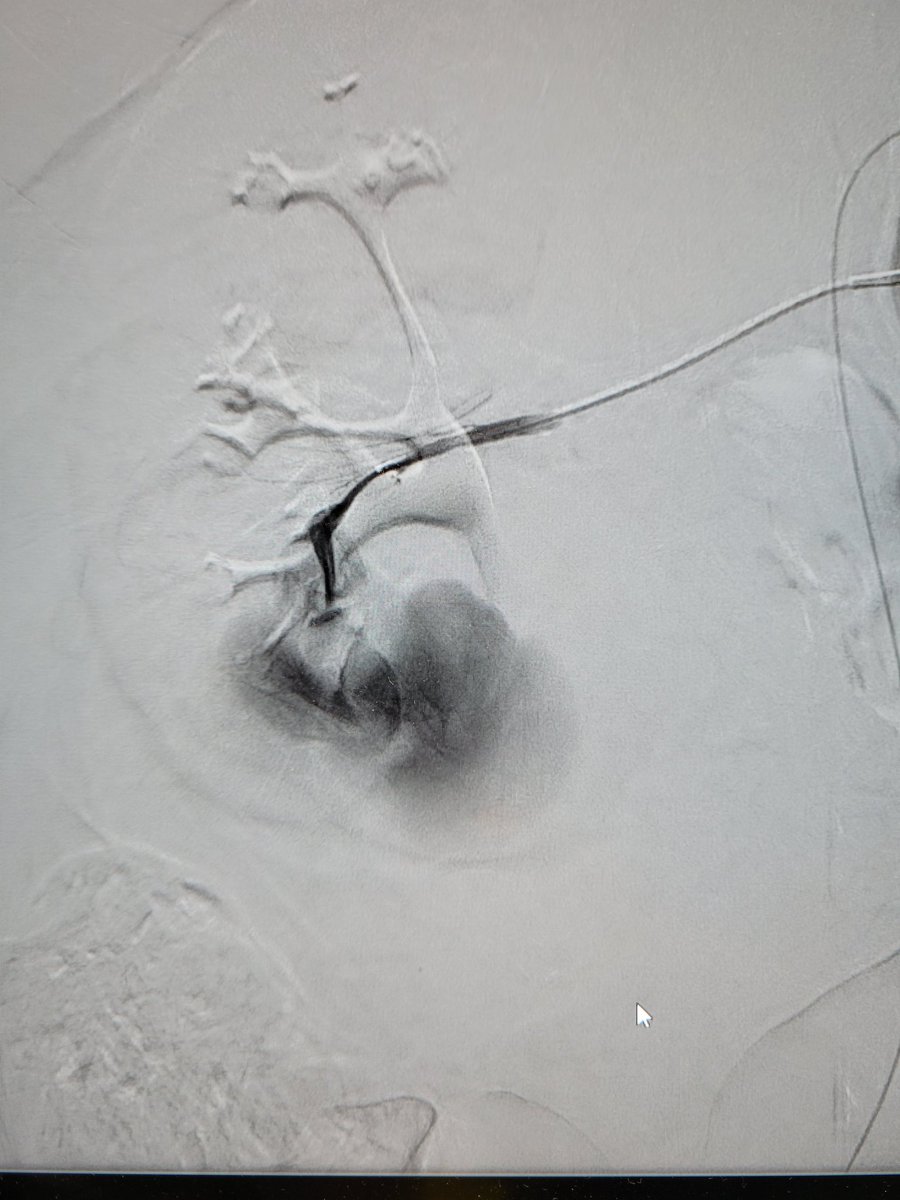

Great case and amazing job #irad #interventionalradiology

Patient presents with abdominal pain and distention found to have an enormous GDA pseudoaneurysm. Emergently taken to IR and coil embolization performed by Dr. Niman. The size is just unbelievable! @TempleRadRes @SIRRFS @SIR_ECS @SIRspecialists #IRAD